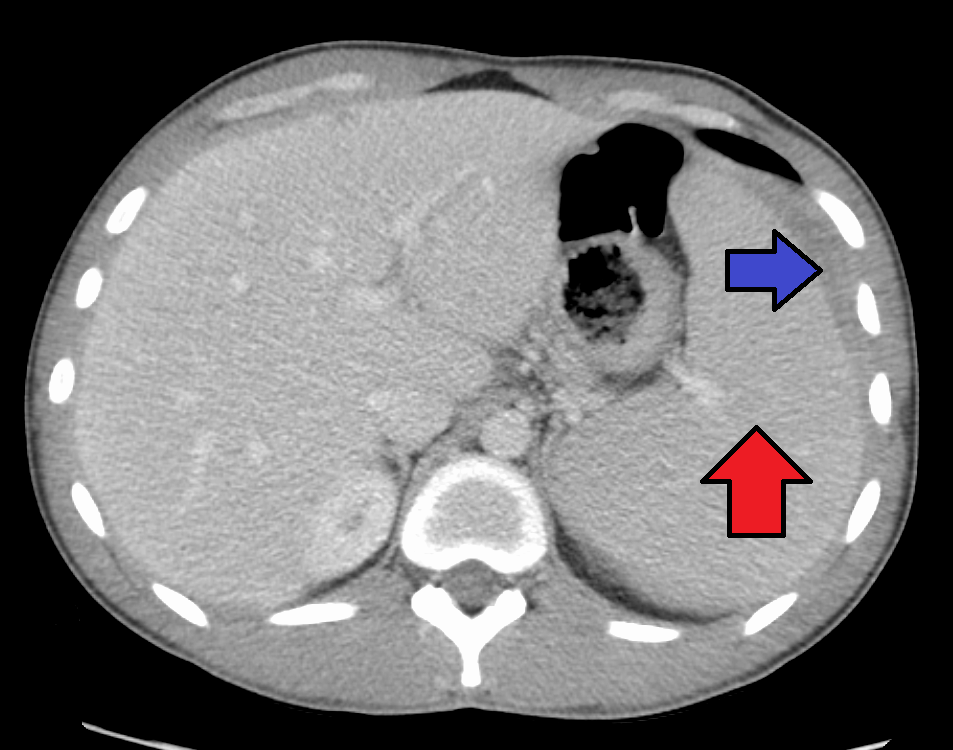

대부분의 감염성 단핵구증은 자연적으로 회복되지만, 드물게 합병증이 나타날 수 있다. 비장 파열, 용혈성 빈혈, 수막염, 뇌염, 횡단척수염, 길랭-바레 증후군 등이 발생할 수 있다.[26][63][64][43][65]비장 비대는 발병 2~3주차에 흔하게 나타나지만, 신체 검사로는 뚜렷하게 나타나지 않을 수 있다. 드물게 비장 파열이 발생할 수 있다.[26] 또한 약간의 간 비대증이 나타날 수 있으며,[23] 황달은 간혹 발생한다.[30][27]

비장 비대와 경부, 겨드랑이, 서혜 림프절의 림프절 종창은 감염성 단핵구증 진단을 의심하는 데 가장 유용하다. 반면에 경부 림프절 종창이 없고 피로가 나타나지 않는다면 감염성 단핵구증이 아니라고 생각할 수 있다. 비장 비대를 감지하는 신체 검사의 무감도는 감염성 단핵구증에 대한 증거로 사용해서는 안 된다는 것을 의미한다.[23] 신체 검사에서 구개의 점상 출혈이 나타날 수도 있다.[23]4. 2. 혈액 검사

비장 파열의 위험을 줄이기 위해 전문가들은 질병 발병 후 최소 3~4주 동안 또는 치료 의사가 결정한 비장 비대 소실 시점까지 접촉 스포츠 및 기타 격렬한 신체 활동, 특히 복부 압력 증가 또는 발살바 수기 (예: 조정 또는 역도)를 피하도록 권고한다.[23][52] 간비종이 심한 경우에는 복부에 충격을 받아 비장 파열이 일어난 사례도 있으므로 안정이 필요하다. 소아 등, 인두통이나 전신 권태감으로 인해 경구 섭취가 불량해진 경우에는 입원하여 수액을 투여할 필요가 있다.